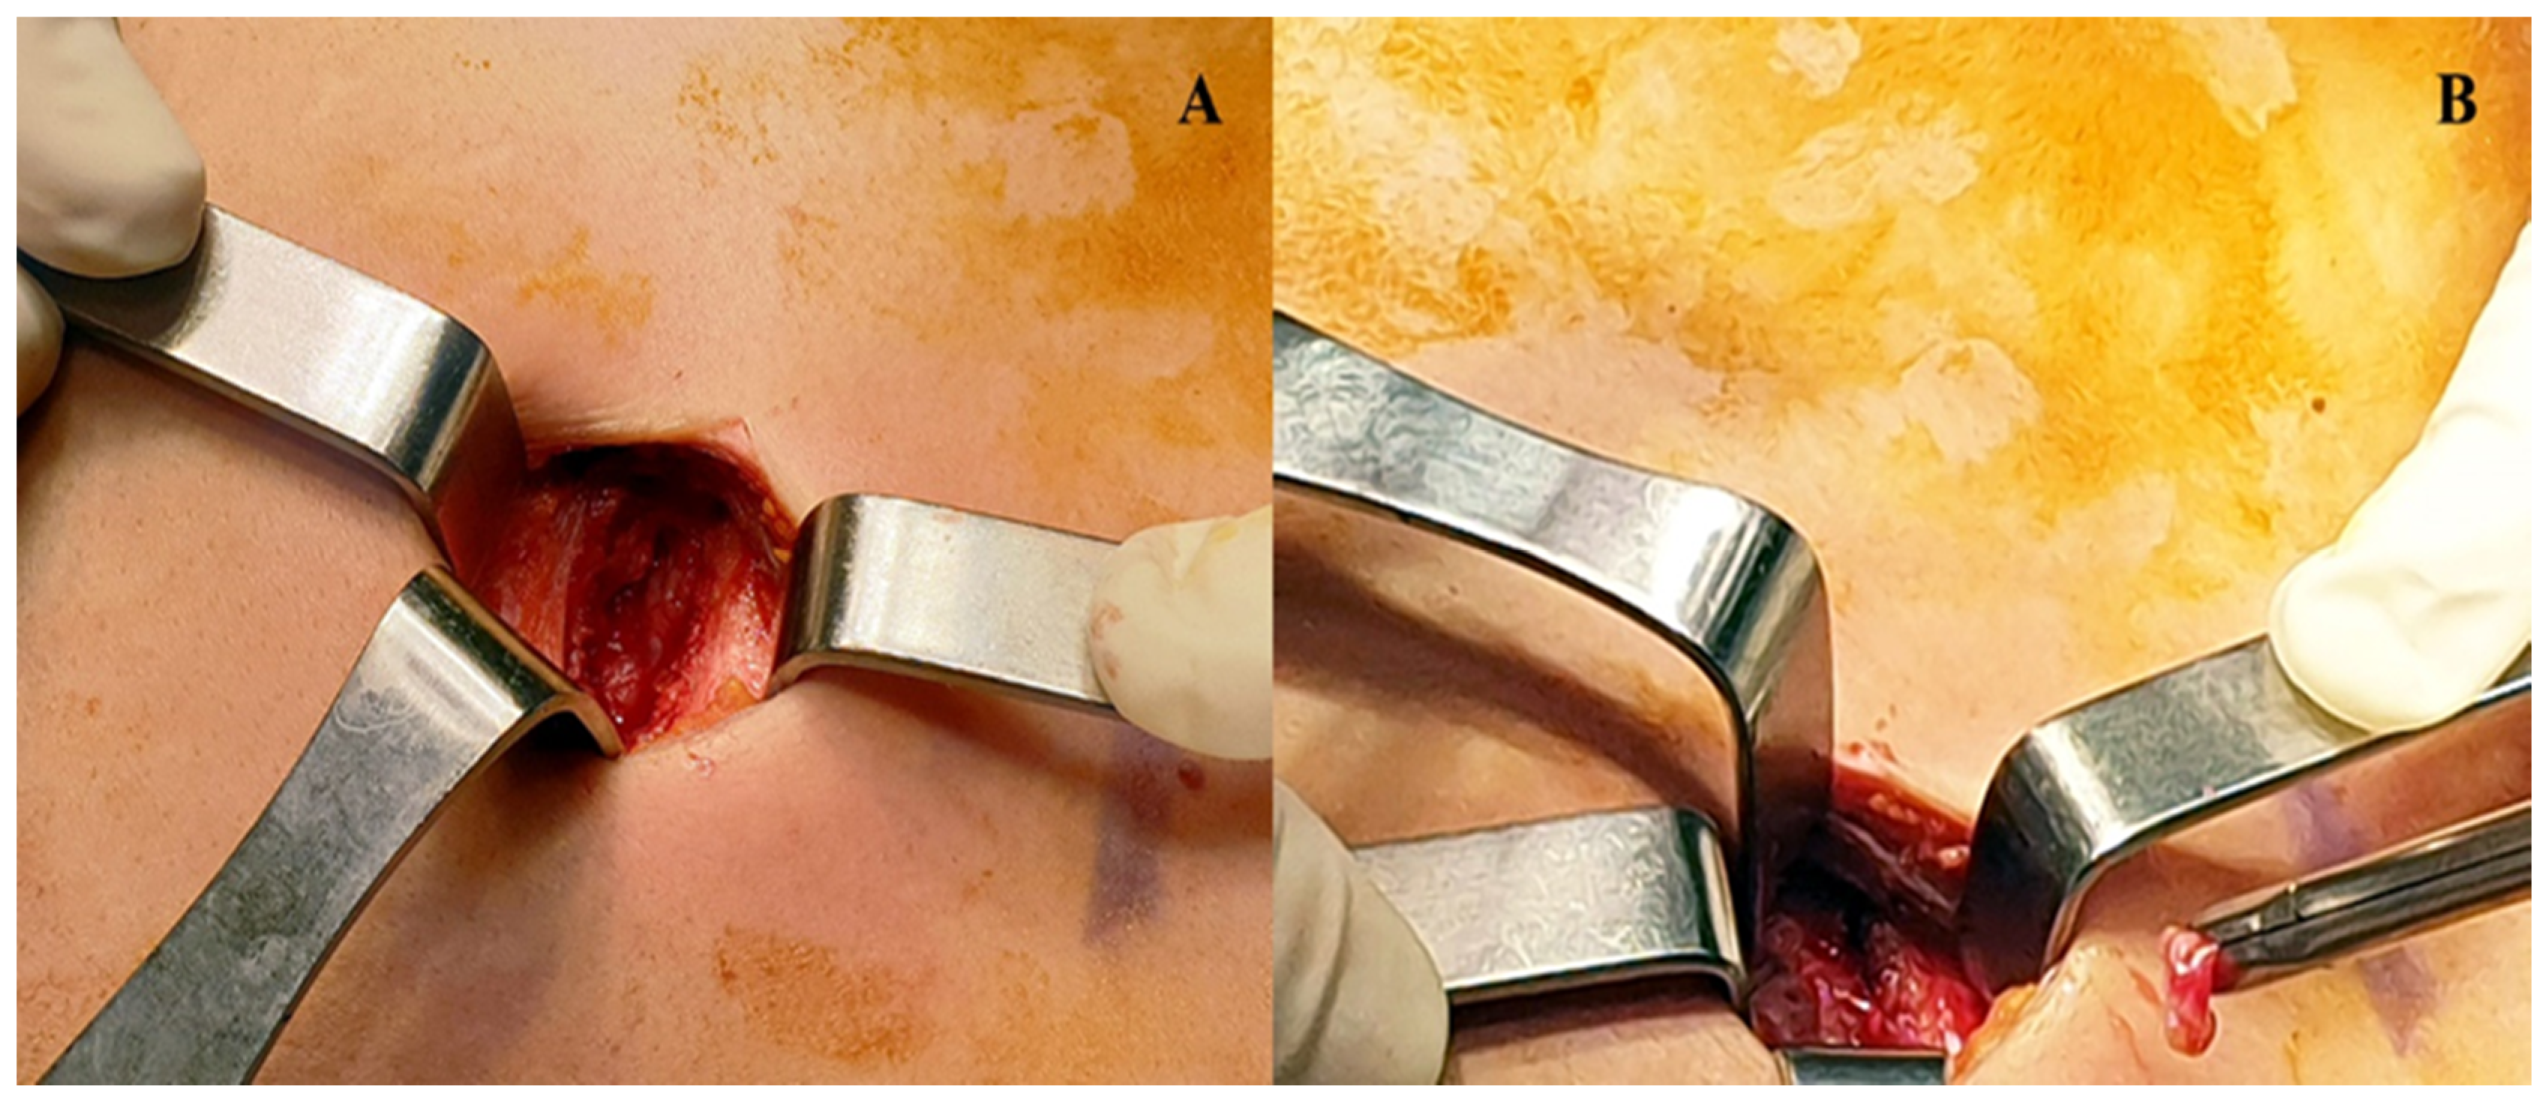

Ultrasonography and Surgical Procedure